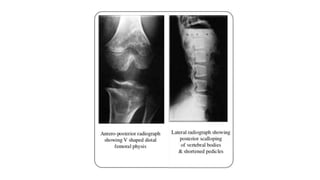

(1) In children, the epiphysis is located

closer to metaphyses leading to an

apparent increase in the depth of the

articular cartilage space.

(3) The two limbs of the V of metaphysis

appear to embrace the epiphysis giving

rise to a ball and socket relationship/

chevron deformity. This appearance is

more common at lower end of femur

and tends to normalise with increasing

age;